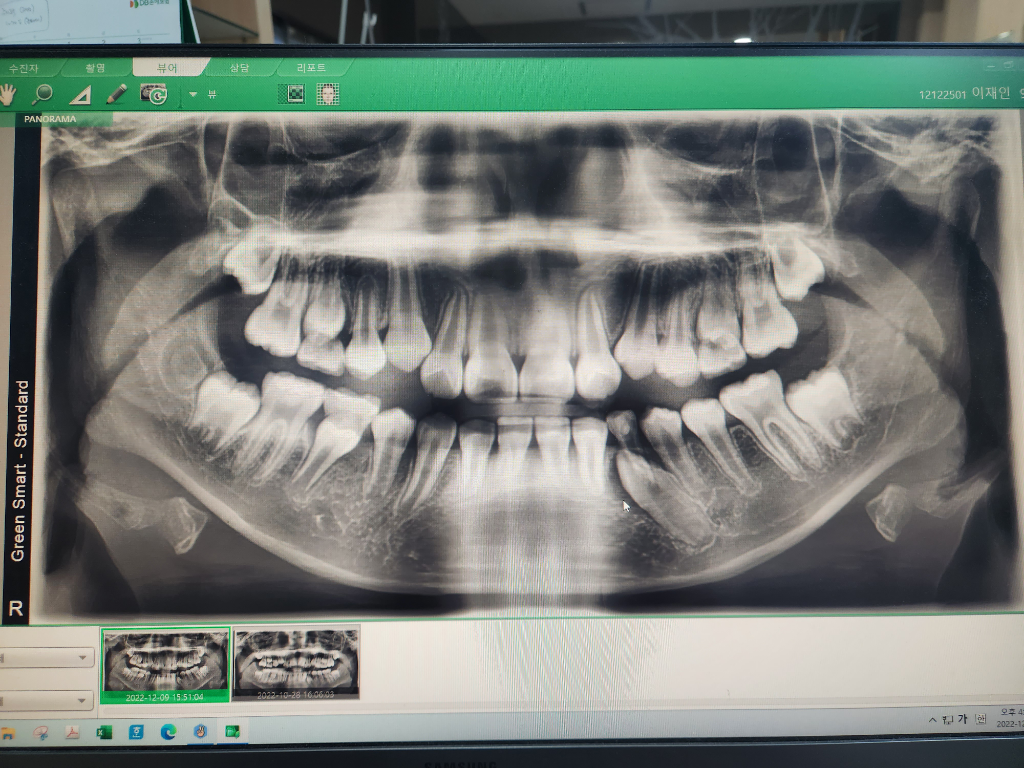

아이 영구치 위치가 자리를 잘 못잡고 옆 치아 뒤쪽으로 나오는것 같은데요

아직 위로 올라오지는 않았는데 뚫고 올라오려는것 같은데 괜찮은걸까요?다른 영구치에 비해서 오래 걸리는것 같아서 언젠가는 올라오겠지..했는데 교정치과 가봐야할지 올라오는것 보고 가도 될지 궁금해요(12세입니다)

1) 보통은 아래턱의 영구치아는 송곳니 -> 작은 어금니 2개 순서로 나오는데 작은 어금니 2개가 먼저 나온 상태이고요

2) 방사선 사진과 현재 사진을 비교해보면, 이전에 영구치 송곳니가 나올 준비가 되기 전에 유치 송곳니를 특정 이유 (충치 등..)로 먼저 빼준 상태이고 영구치 송곳니가 미처 나오기 전에 양 옆 앞니와 어금니가 약간 옆으로 쓰러지면서 현재 송곳니가 나올 공간이 살짝 부족하긴 합니다.

3) 다만, 송곳니가 정상적으로 나올지는 3개월 정도면 확인이 가능합니다. 맹출력이 있기 때문에 아예 못나오지는 않고 옆으로 회전하면서 나오거나 아니면 주변 치아가 조금씩 이동하여 정상적으로 자리를 잡을 수도 있습니다.

4) 먼저 선제적 개입을 해주고 싶다면 교정 치과나 소아 치과 등에서 공간확장 장치를 고려해볼 수 있습니다.